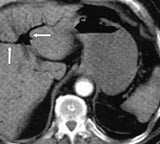

Ved ankomst i sykehuset var han kaldsvettende, forvirret og klaget over smerter i venstre bein. Han hadde ikke buksmerter. Han hadde puls 190/min, uregelmessig, systolisk blodtrykk 210 mm Hg og normal kroppstemperatur. Buken var lett utspilt, uten ømhet eller andre tegn på peritonitt. Venstre bein hadde nedsatt sirkulasjon. EKG viste raskt atrieflimmer. Pasienten var kritisk syk. Behandling av hans raske atrieflimmer med verapamil og metoprolol bedret ikke situasjonen. Blodprøver viste Hb 19,0 g/100 ml (jf. 17,4 g/100 ml to måneder tidligere), leukocytter 21,7 × 10 9 /l, trombocytter 226 × 10 9 /l, CRP 138 mg/l, natrium 141 mmol/l, kalium 3,3 mmol/l, albumin 42,3 g/l, kreatinin 140 µ mol/l, bilirubin 25 µ mol/l, ASAT 262 U/l, ALAT 139 U/l, CK 227 U/l, amylase 139 U/l. CT abdomen viste en normalt kalibrert aorta med tromber i venstre a. iliaca og i a. mesenterica superior. Det forelå en fyllingsdefekt nær avgangen av truncus coeliacus, samt fravær av kontrastfylling i coeliacusgebetet. Forgrening av luft var synlig i leveren (fig 1), helt ut til leverkapselen (fig 2). Luft var også synlig i den ekstrahepatiske del av portvenen, samt i miltvenen og i mesenteriale vener (fig 3). Det forelå ingen utvidelse av magesekken, og heller ingen intramural luft. Vi mistenkte en vaskulær katastrofe i buken. På vei til operasjonsstuen mistet pasienten bevisstheten og døde.

Det er alminnelig anerkjent at luft som forgrener seg lenger distalt enn 2 cm fra leverkapselen, gjengir et luftportogram, snarere enn et luftkolangiogram (1 – 3). Det sistnevnte er et hyppigere og mindre illevarslende funn. Luftportogram er også kjent i engelskspråklig litteratur som ”hepatic portal venous gas”, forkortet HPVG. Luftportogram er beskrevet i forløpet av en rekke ulike abdominale katastrofer, oftest i forbindelse med tarmnekrose (4, 5), og er med få unntakelser et varsel om elendig prognose (1). Tidligere ble dette tegnet alene sett på som tilstrekkelig indikasjon for øyeblikkelig laparotomi (1, 6). I den senere tid er det publisert enkelte rapporter om mindre kritiske tilstander som også har ført til danning av luft i portvenesystemet, spesielt inflammatoriske tarmsykdommer, både spontant og etter endoskopi/røntgen colon (7 – 9), tarmparalyse (10), dilatasjon av ventrikkelen (11, 12), divertikulitt med abscessdanning (2, 13 – 16) og tarmobstruksjon (17). Det kan også være et resultat av stumpt eller penetrerende traume (18 – 20). Skader av mucosa og distensjon av ventrikkel/tarm antas å være disponerende faktorer. Tilstander i ventrikkelen er sjelden årsak til luft i portvenesystemet. Blant disse er lokale infeksjoner og gastrisk emfysem. Sistnevnte beskriver tilstander der luft er presset inn i ventrikkelveggen på grunn av intraluminal dilatasjon, oftest iatrogent, obstruktivt eller traumatisk betinget (21, 22). Prognosen er utmerket.